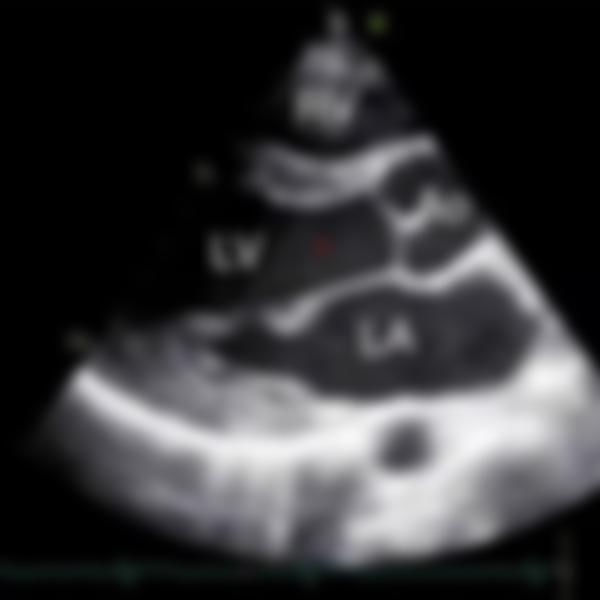

64.下圖為心臟超音波胸骨旁長軸(PLAX)影像,標號1的解剖部位應為:

(A)右心室(RV)

(B)左心室(LV)

(C)主動脈瓣(AV)

(D)左心房(LA)